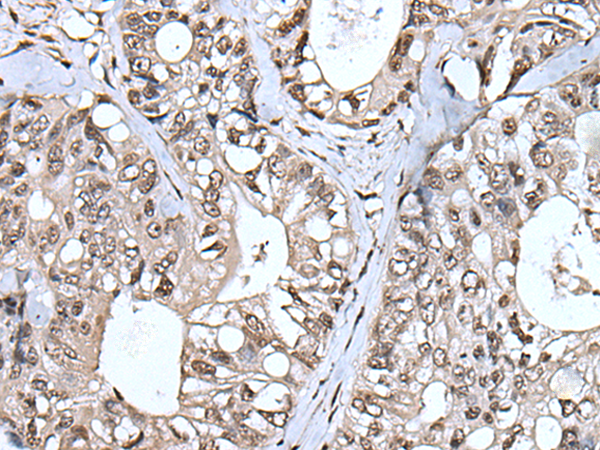

IHC positive control: |

Human colorectal cancer and human tonsil |